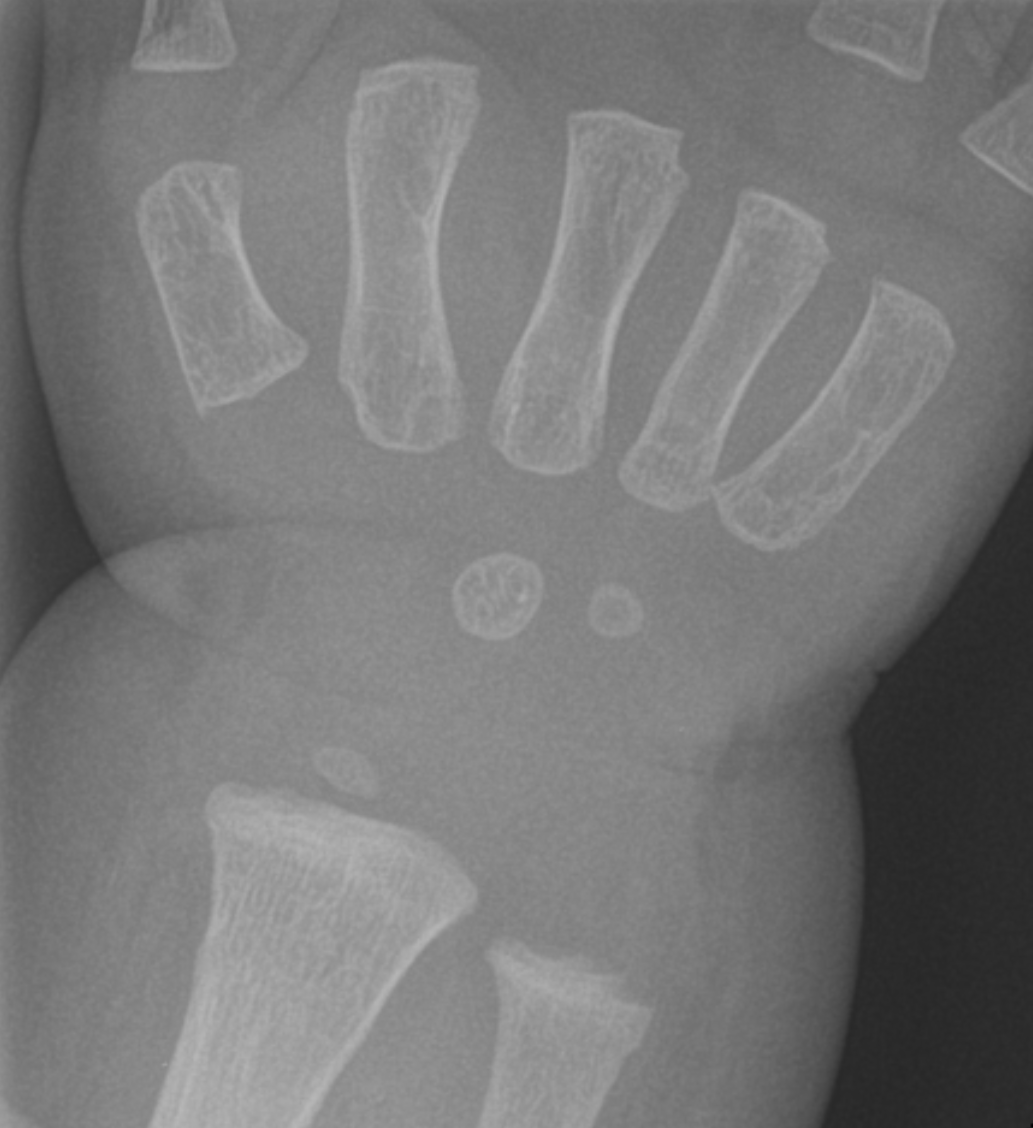

Distal radius fracture